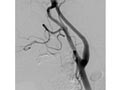

Una angiografía de la cabeza y del cuello es una prueba de rayos X que utiliza un tinte especial y una cámara (fluoroscopio) para tomar imágenes del flujo de sangre en los vasos sanguíneos de la cabeza y del cuello. Puede utilizarse una angiografía del cuello (angiografía carotídea) para observar las grandes arterias en el cuello que se dirigen al cerebro. Puede utilizarse una angiografía de la cabeza (angiografía cerebral) para observar las venas o las cuatro arterias (estudio de cuatro vasos) que llevan sangre al cerebro.

Durante una angiografía, un tubo delgado y blando que se llama catéter se coloca en un vaso sanguíneo de la ingle o justo por encima del codo. El catéter es guiado a la zona de la cabeza y el cuello. Luego, se inyecta un tinte de yodo (material de contraste) en el vaso sanguíneo para hacer que la zona se vea de manera nítida en las imágenes radiográficas. Las imágenes de la angiografía pueden presentarse en placas de radiografías regulares o pueden guardarse como imágenes digitales en una computadora.

Una angiografía puede detectar una protuberancia en un vaso sanguíneo (aneurisma). También puede mostrar el estrechamiento o la obstrucción de un vaso sanguíneo que hace más lento o detiene el flujo de sangre. Puede verse un patrón anormal de los vasos sanguíneos (malformación arteriovenosa [AV]) o vasos anormales cerca de un tumor.